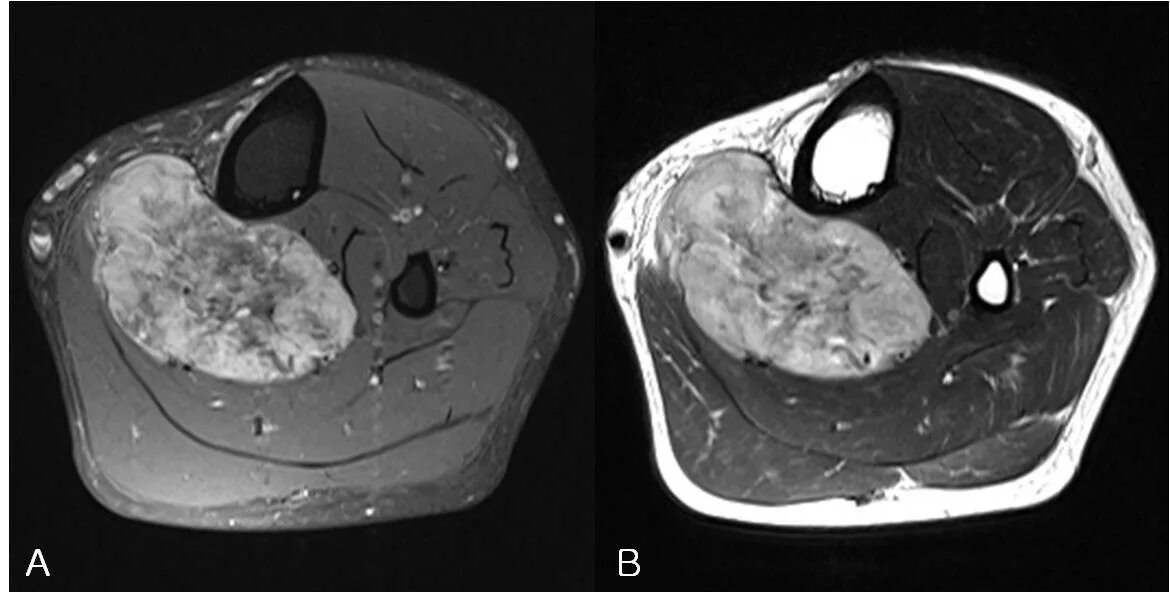

Саркома мрт